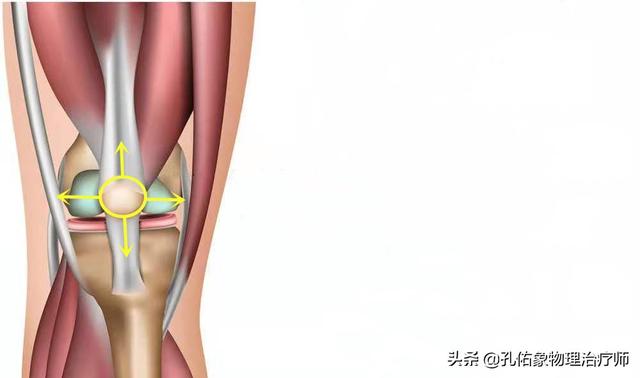

L'articulation du genou comporte deux ménisques, l'un médial et l'autre latéral. Le ménisque médial est relié au ligament collatéral médial et à la capsule articulaire médiale, tandis que le ménisque latéral est relié à la capsule articulaire latérale ; le quadriceps, le muscle semi-membraneux et le muscle poplité, à l'arrière, sont également reliés au ménisque. Le ménisque est une structure très importante de notre corps, qui non seulement approfondit la profondeur de la fosse articulaire, rend la connexion entre l'os de la cuisse et l'os du mollet plus adaptable et augmente la stabilité de l'articulation du genou, mais protège également l'articulation du genou et agit comme un coussin pour amortir les chocs.

Cependant, dans la vie de tous les jours, lesLe ménisque est souvent négligé, mais les douleurs du genou y sont liées d'une manière ou d'une autre !. Pour mieux le connaître, il faut aussi connaître l'apport nutritionnel du ménisque :

Le ménisque s'appuie fortement sursang和liquide synovial dans la capsule articulaire (médecine)Deux substances principales sont fournies : le tiers externe du ménisque est irrigué par le sang et une petite partie est située au centre, tandis que le tiers interne est dépourvu de sang et dépend principalement du liquide synovial de la capsule articulaire pour son alimentation.

Si le ménisque a dégénéré, il peut être endommagé lorsque vous vous accroupissez par inadvertance ou lorsque vous vous levez et faites pivoter votre corps. Il est évident que les problèmes d'irrigation sanguine, d'amortissement et de liquide synovial contribuent directement à la froideur, à la douleur et au cliquetis que vous ressentez lorsque vous bougez.

Lorsque l'on étire le genou, on constate que la rotule se déplace avec la flexion et l'extension de l'articulation du genou, et que le son émis lors de la flexion et de l'extension de l'articulation est en fait lié au mouvement de la rotule. Sous la rotule se trouve ce que l'on appelle le corps adipeux infrapatellaire, qui est un élément important de la structure de l'extension de l'articulation du genou ; le corps adipeux infrapatellaire a un effet amortisseur dans le mouvement et permet de conserver une structure harmonieuse pour le mouvement d'extension de l'articulation du genou.

D'une manière générale, ce type de structure peut entraîner une certaine usure lors de l'utilisation répétée de l'articulation du genou, ce qui a un impact sur son mouvement, et un bruit de cliquetis lors du mouvement peut en être l'une des manifestations.